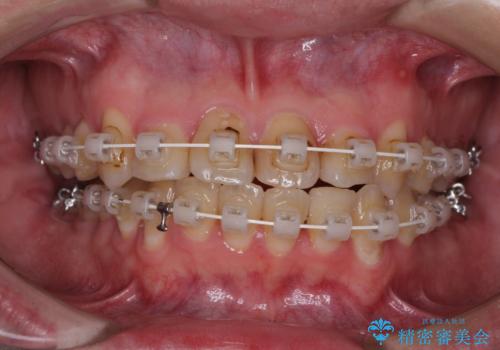

クロスバイトは、治療の過程で咬み合わせが大きく変化する期間があり、食事が取りにくくなってしまいます。

また、装置が対合歯と咬み合ってしまい、頻繁に脱落するなど、色々と面倒なことがあり、治療がスムーズに進まないことがあります。